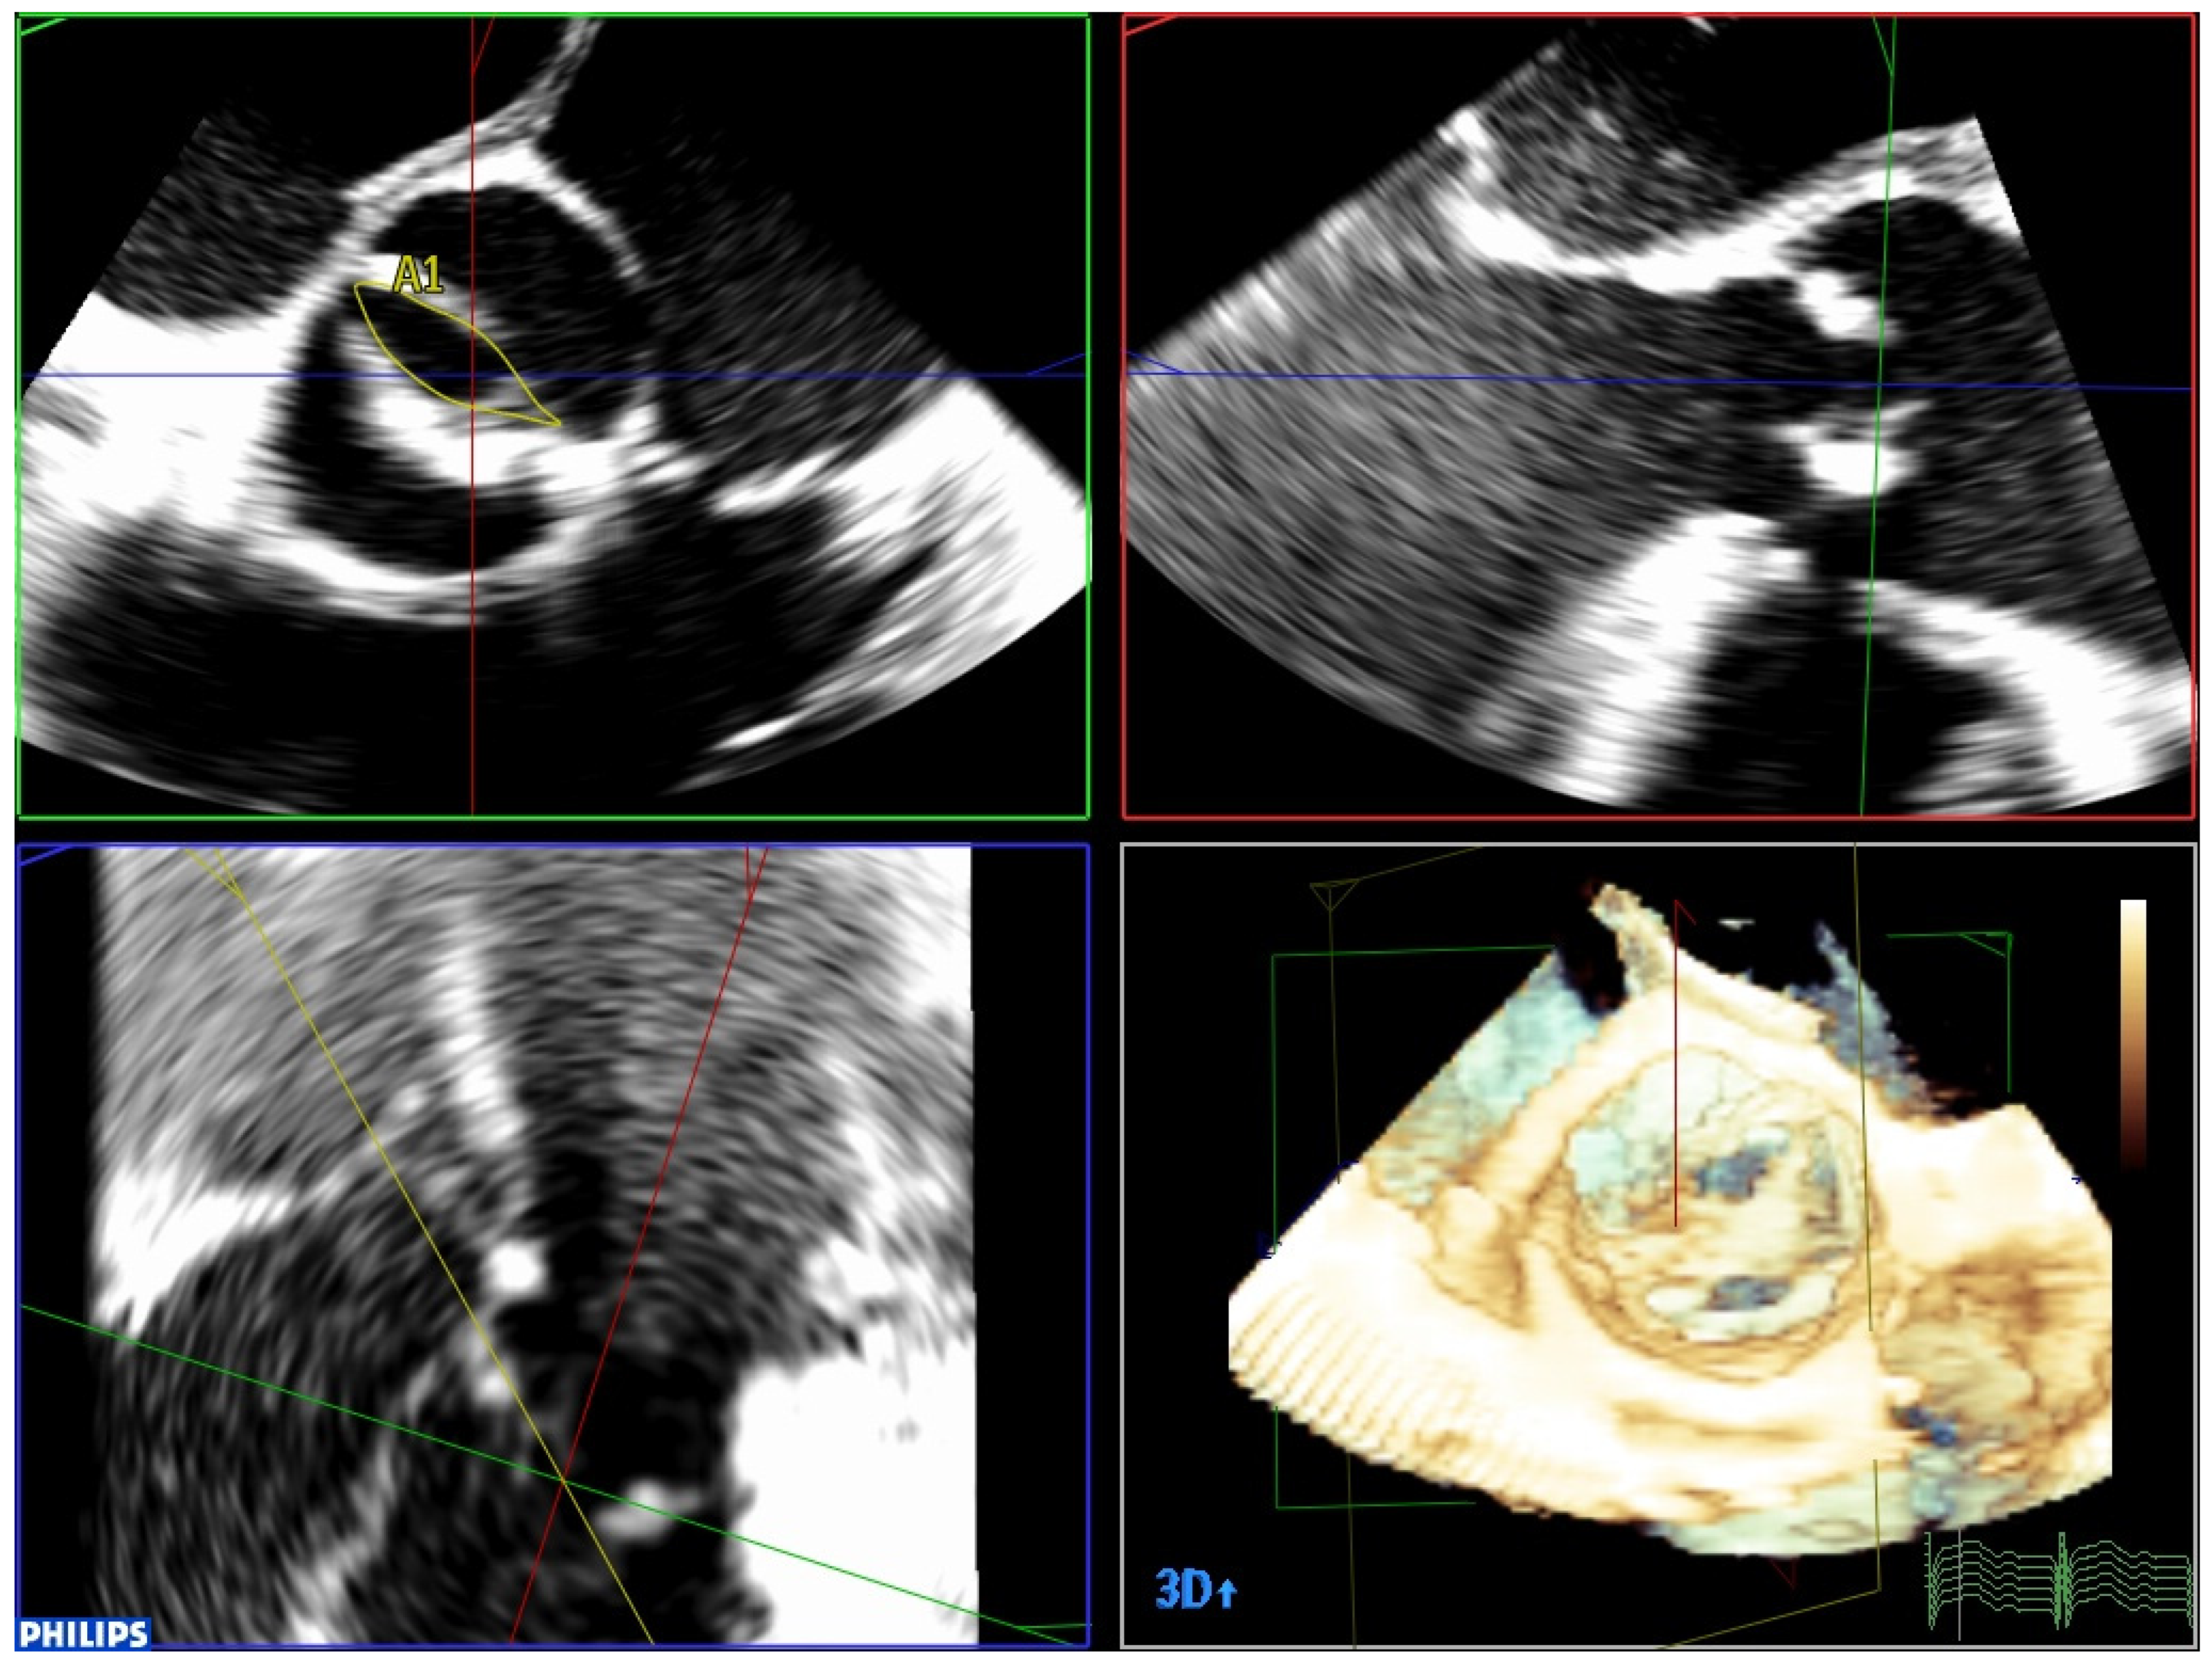

Figure 1.

Three-dimensional TEE image using MPR mode in a patient with a bicuspid aortic valve. It makes it possible to perfectly visualize the existence of only two leaflets, as well as accurately measure the valve opening area.

Three-dimensional TEE is also useful in cases of clinical–echocardiographic discrepancies, such as in situations of severe low-gradient aortic stenosis where there are doubts about the severity of the stenosis. The higher quality of the TEE images provides a more accurate assessment of the degree and extent of valvular calcification, the mobility of the leaflets, and the degree of valve opening than transthoracic echocardiography (Video S3). The planimetry of the orifice using TEE is more precise than if it is performed using transthoracic echo, and in this case 3D-TEE is especially useful. Three-dimensional technology allows data pyramids to be obtained in the 30° × 60° scan sectors. Post-processing allows the reconstruction of any plane and angle of the pyramidal volume previously obtained, and to obtain the valve opening area at the level of the valve cusps, whether it is a trileaflet or bicuspid valve (Figure 1 and Figure 2). TEE can also make it possible to obtain very reliable gradients in transgastric projection (Figure 3), as well as making a more precise measurement of the diameter of the left ventricular outflow tract (LVOT). It should also be explored whether there are mobile calcium elements that could become detached during the procedure, and their relationship with the coronary ostia, due to the risk of their occlusion during the implant. It must be ruled out that there are no additional processes, such as endocarditis, which we can identify by the presence of vegetations. The presence and severity of aortic valve regurgitation should also be reflected. A complete TEE should also include assessment of left ventricular function and the possible existence of intraventricular thrombi that could cause embolic complications during the procedure. Atheromatosis of the thoracic aorta (Video S4) can also increase embolic risk during the procedure, especially if it is transfemoral. Mitral valve function should also be assessed, and if mitral regurgitation exists, its severity should be established.

Measurement of the aortic valve area by 3D planimetry in a patient with a trileaflet aortic valve.